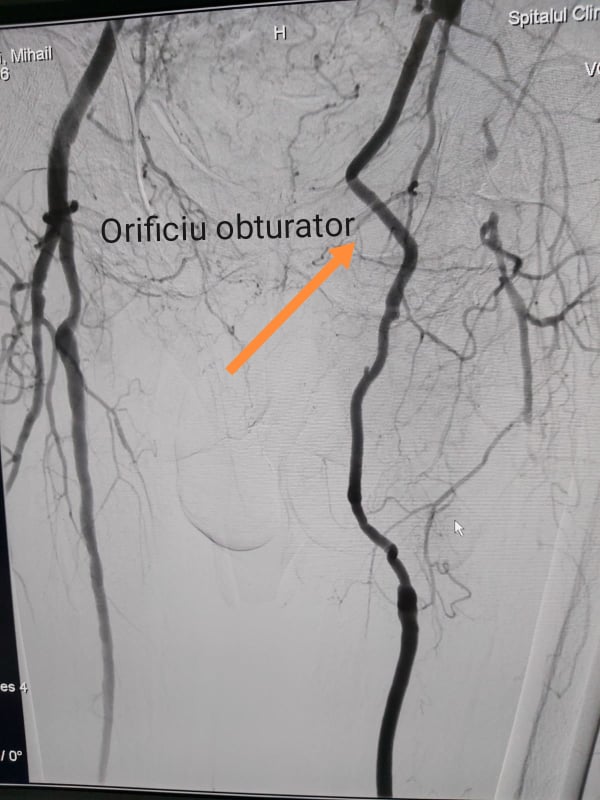

”Orificiu obturator posedă o formațiune anatomică ”delicată” din punct de vedere anatomic şi chirurgical, care se numește ”corona mortis”- zonă de conexiune a colateralelor vaselor bazinului mic, prin care la trecerea bypass-ului (șuntului), pot fi lezate, ceea ce se poate solda cu hemoragie greu controlabilă (pierdere mare de sânge) care poate pune în pericol viața pacientului. Plaga infrainghinală postoperator a fost tratată în mod deschis prin pansamente locale zilnice, cu cicatrizarea secundară” a declarat chirurgul vascular, Emelian Oțel.